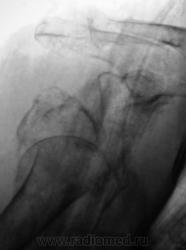

По сравнению со снимками до репозиции определяется гипсовая повязка, в остальном - без динамики

Бесформенность между головкой и впадиной - фрагмент плечевой кости. Репозиция никакая.